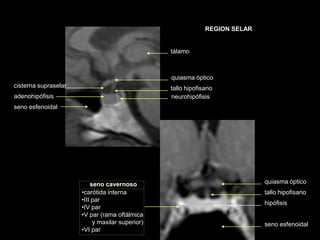

REGION SELAR

adenohipófisis neurohipófisis

seno esfenoidal

tallo hipofisario

quiasma óptico

tálamo

cisterna supraselar

seno cavernoso quiasma óptico

hipófisis

•carótida interna

•III par

•IV par

•V par (rama oftálmica

y maxilar superior)

•VI par